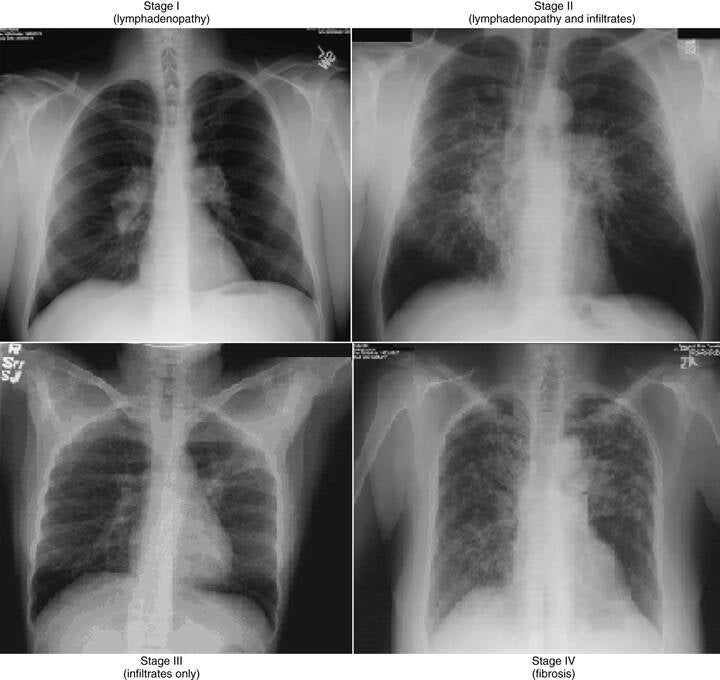

Prvi stadij sarkoidoze ukazuje na granulome u limfnim čvorovima.

Drugi stadij ukazuje na zahvaćenost limfnih čvorova uz granulome u plućima. U početku bi se ovo moglo činiti progresivnom dijagnozom u usporedbi s prvim stadijem.

Međutim, treći stupanj sarkoidoze ukazuje na granulome prisutne u plućima, ali ne i u limfnim čvorovima. Ovo pokazuje kako faze nisu progresija.

Četvrti stupanj sarkoidoze je malo drugačiji od ostala tri. Stadij četiri ukazuje na ožiljke u plućima - plućnu fibrozu - koja je nepovratna. Zbog toga je četvrta faza najteža manifestacija sarkoidoze. Ovo također doprinosi pogrešnom mišljenju da stadiji sarkoidoze slijede progresiju.